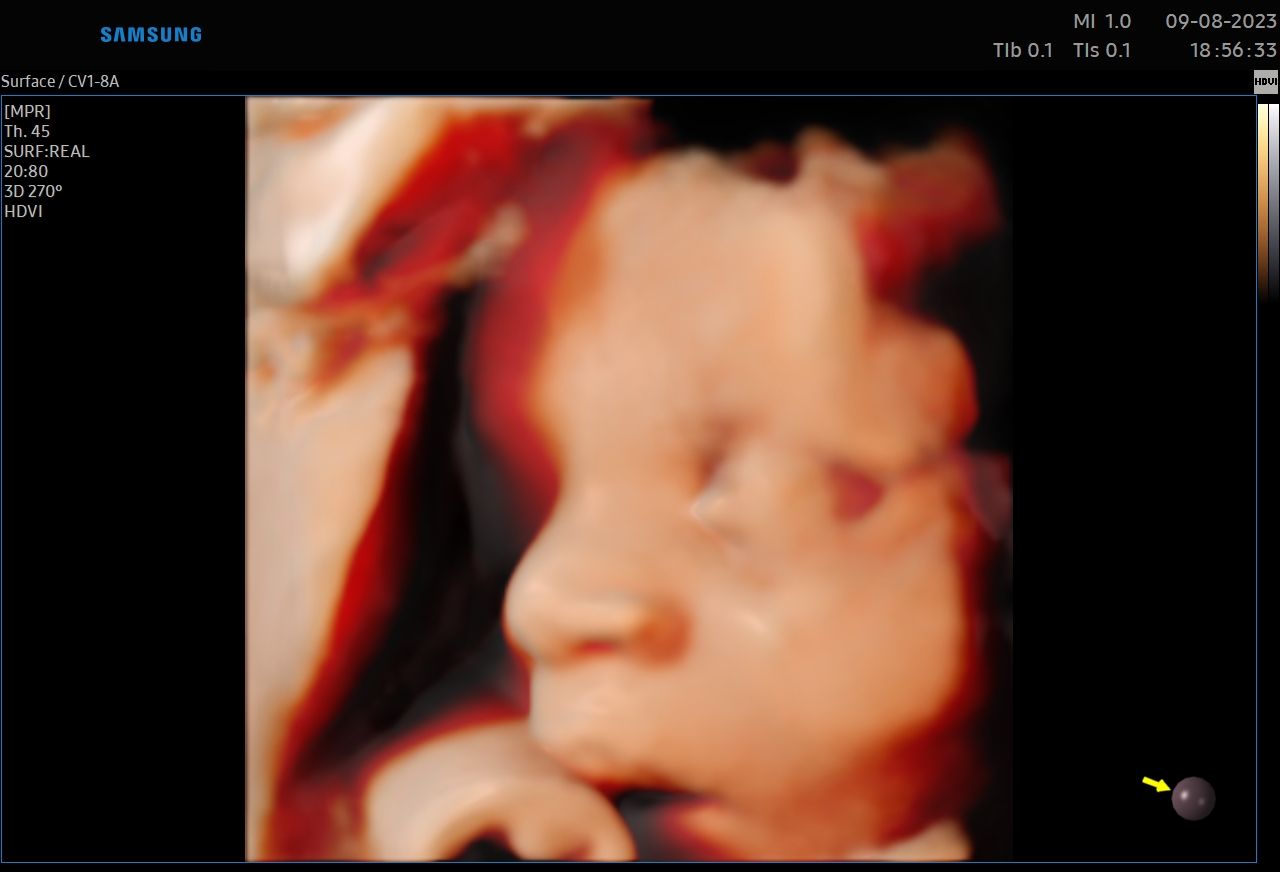

:-) Jestem lekarzem specjalistą w zakresie ginekologii i położnictwa , w ramach prowadzonej praktyki ginekologicznej staram się świadczyć kompleksowe porady lekarskie najwyższym poziomie ,w oparciu o najwyższe standardy jak i przy pomocy najnowszego sprzętu medycznego. W trakcie pracy zawodowej uzyskałem kolejno tytuły specjalisty I stopnia , a później specjalisty II stopnia , a także uzyskałem dodatkowe uprawnienia

CERTYFIKAT BADAŃ PRENATALNYCH POLSKIEGO TOWARZYSTWA GINEKOLOGÓW I POŁOŻNIKÓW

CERTYFIKAT BADAŃ PRENATALNYCH FMF ( FETAL MEDICINE FOUNDATION - LONDYN )

W ramach praktyki wykonuję pełen zakres badań ultrasonograficznych w zakresie ginekologii jak i położnictwa wraz z badaniami prenatalnymi , badaniami ultrasonograficznymi piersi .

Zdjęcia i filmy